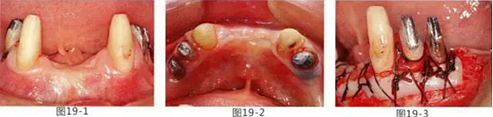

有少數(shù)牙體殘存的病例,需要進行修復處理,將基牙和鉤牙部位的牙周袋去除以及對頰舌側(cè)進行FGG(游離齦移植)來獲取附著齦的病例

圖19-1 右下3,4,左下3,4,5殘存牙頰側(cè)面照。唇頰側(cè)沒有附著齦。

圖19-2 同部位的舌側(cè)面照。雖然有1mm左右角化牙齦,但是進行預測切開的話,會使角化牙齦完全消失。

圖19-3 左下3,4,5部位進行FGG(游離齦移植)去除牙周袋以及獲得附著齦。同時進行骨外科處理。相反側(cè)也進行同樣的處理。